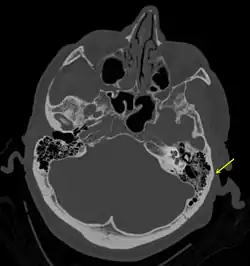

Basilar skull fracture

A basilar skull fracture is a break of a bone in the base of the skull.[1] Symptoms may include bruising behind the ears, bruising around the eyes, or blood behind the ear drum.[1] A cerebrospinal fluid (CSF) leak occurs in about 20% of cases and may result in fluid leaking from the nose or ear.[1] Meningitis occurs in about 14% of cases.[2] Other complications include injuries to the cranial nerves or blood vessels.[1]

A basilar skull fracture typically requires a significant degree of trauma to occur.[1] It is defined as a fracture of one or more of the temporal, occipital, sphenoid, frontal or ethmoid bone.[1] Basilar skull fractures are divided into anterior fossa, middle fossa and posterior fossa fractures.[1] Facial fractures often also occur.[1] Diagnosis is typically by CT scan.[1]

Temporal bone fractures

Acute injury to the internal carotid artery (carotid dissection, occlusion, pseudoaneurysm formation) may be asymptomatic or result in life-threatening bleeding. They are almost exclusively observed when the carotid canal is fractured, although only a minority of carotid canal fractures result in vascular injury. Involvement of the petrous segment of the carotid canal is associated with a relatively high incidence of carotid injury.[10]